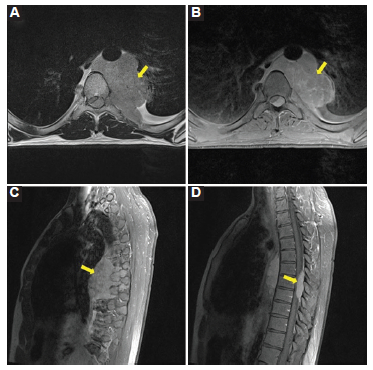

Se realizó una resonancia magnética (RM) de columna vertebral para evaluar un posible compromiso de la médula espinal, en la que se evidenció la tumoración en el mediastino posterior, isointensa en las secuencias potenciadas en T2, con realce moderado y homogéneo tras la inyección de gadolinio. La misma se introducía al interior del canal raquídeo y provocaba una marcada compresión de la médula espinal dorsal, desplazándola en sentido anterior y lateral (Fig. 3).